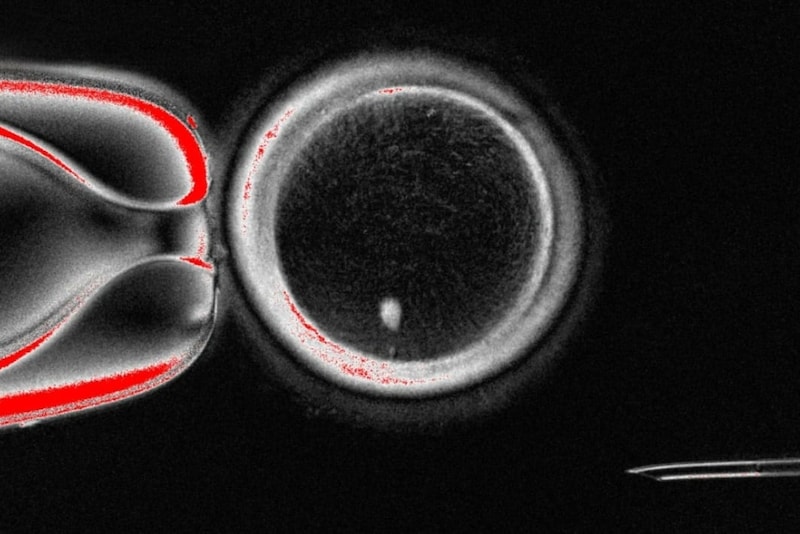

次は、この人工卵子に顕微授精(ICSI)で精子を注入するステップです。

研究チームは実験全体で約82個の卵子を作製し受精させ、その結果を追跡しました。

正常に受精が進んだことを示す「前核」(受精後に現れる核)が確認できたのは、全体のうち約17%(ICSIのみ条件の平均)でした。

つまり、受精させた卵子の中でも、ごく一部だけが最初のステップを正しく踏み出せたことになります。

さらに追加培養を行うと、約9%(約7~8個)が胚盤胞の段階に成長したことがわかりました。

胚盤胞とは、受精後5〜6日目に見られる小さなシャボン玉のような構造で、内側には「内部細胞塊」という将来の胎児になる細胞の塊があり、その周囲を胎盤になる細胞が取り囲んでいます。

体外受精(IVF)などの不妊治療でも、この胚盤胞まで正常に成長できた胚は、その後の発育が順調な可能性が高いことが知られているため、重要なチェックポイントとされています。

今回の研究では倫理的配慮のため、この段階で培養を中止し、子宮への移植は行われませんでした。

さらに、この胚盤胞を詳しく分析したところ、皮膚細胞由来の染色体と精子由来の染色体が同じ細胞に統合されていることが確認されました。

ただし、個々の胚の中には細胞ごとに染色体構成が異なる「モザイク」状態のものもあり、完全に安定した遺伝構造を持つ胚はまだ少ないこともわかりました。